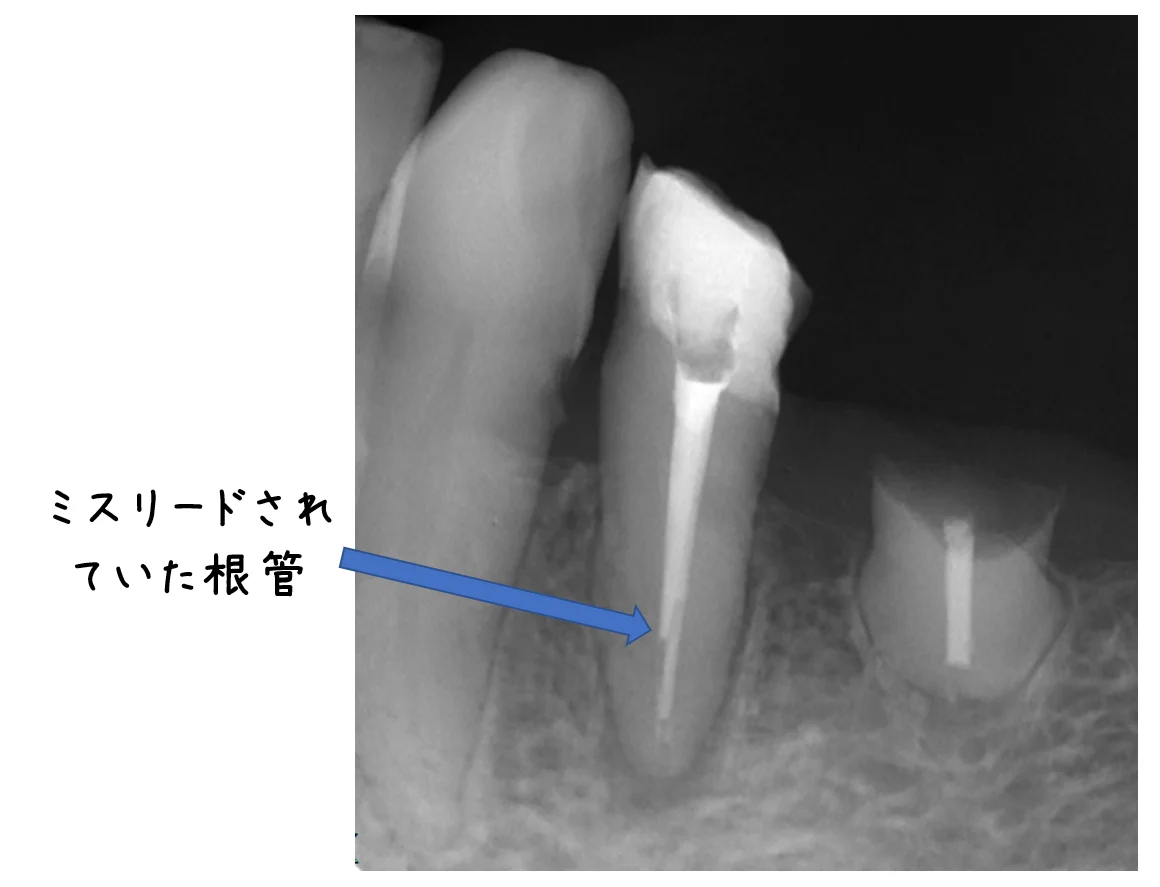

初診時のレントゲンがこちらです。

【2日目】 最初にレントゲンを見た時に「なんか根管の上の方しか触られた形跡がないなぁ・・・」と思いましたが・・・ 嫌な予想は的中するもので、どうやら本来の根管とは別の方向に穴を開けようと進めていたようで、もう少しで明後日の方向に穴が開くところでした・・・。 とりあえず、その日のうちに本来の根管を見つけ、形態を整えることに。

お薬が2本見えていますが、そのうち短い方が明後日な方向にミスリードされていた根管です。